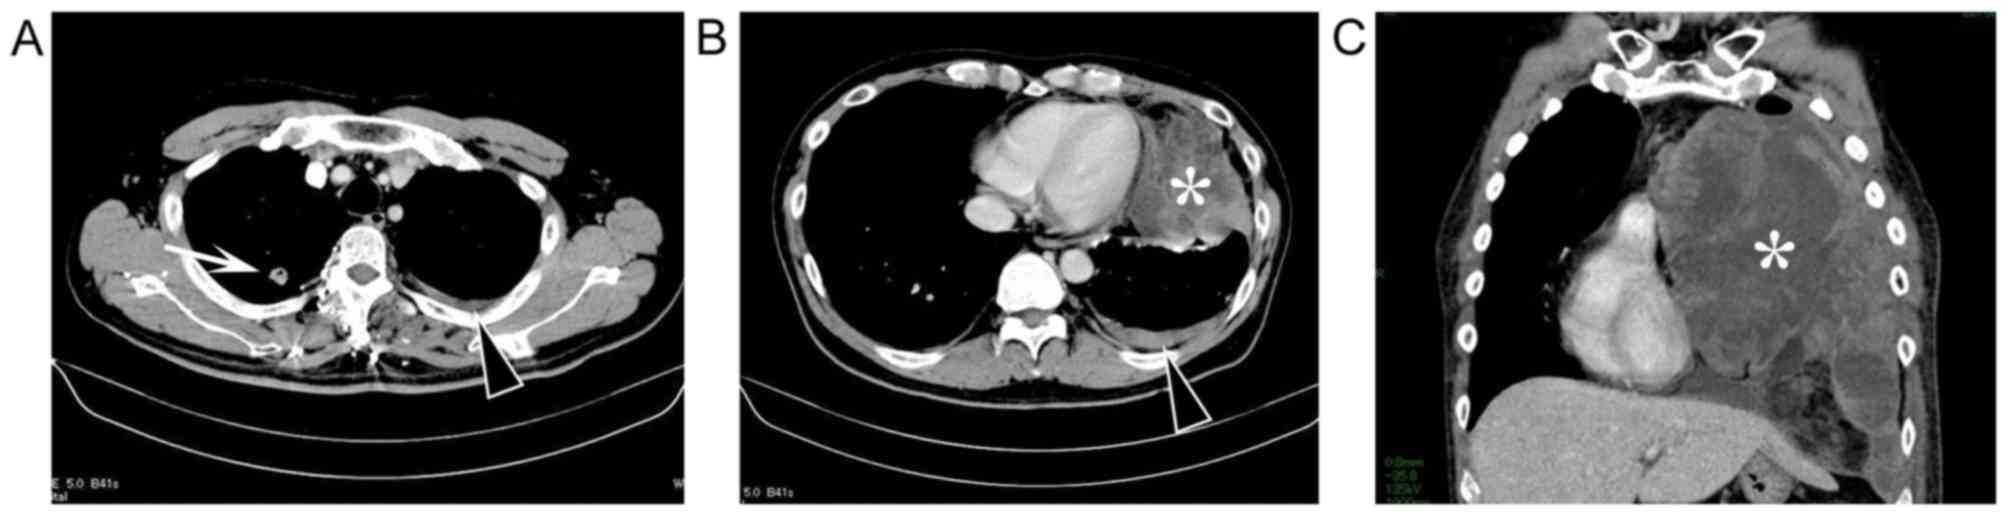

Pleural Dedifferentiated Liposarcoma A Case Report